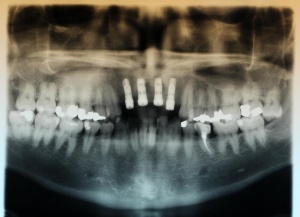

Nach Genehmigung des Antrages erfolgte im März 2012 die Extraktion aller Zähne (Abb. 1).

Im Oberkiefer konnten mit der Planungssoftware SkyPlanX der Firma Bredent 6 Implantate mit BoneSplit geplant werden (Abb. 2), im Unterkiefer war eine Implantation aufgrund ungenügenden Knochenangebots nicht möglich.

Im August 2012 erfolgten die 3D-gestützte Implantation (6 Implantate, Firma Nobel Biocare, System Active) im Oberkiefer mit Bone Split sowie eine An- und Auflagerungsosteoplastik vom linken Beckenkamm im Unterkiefer nach Entfernung der Miniimplantate (Abb. 3). Nach komplikationsloser Einheilung wurde im Dezember 2012 die Materialentfernung und Implantation im Unterkiefer (6 Implantate, Firma Nobel Biocare, System Active) durchgeführt (Abb. 4). Die Osseointegration verlief ungestört. Aufgrund der ungenügenden Weichgewebssituation im Unterkiefer erfolgte an jedem Implantat bei Freilegung eine Vestibulumplastik mit Einlagerung einer bioresorbierbaren Membran (Firma Botiss, Mucoderm, Abb. 5 und 6). Die endgültige prothetische Versorgung erfolgte durch den truppenzahnärztlichen Kollegen in der Stammeinheit des Patienten (Zahnarztgruppe Nordholz / SanZ Celle) mit einer gaumenfreien implantatgetragenen Teleskopprothese im Ober- und Unterkiefer, die eine festsitzend-herausnehmbare vollständige stomatognathe Rehabilitation des Patienten ermöglichte (Abb. 7 und 8). Er wurde zum halbjährlichen Recall angehalten.